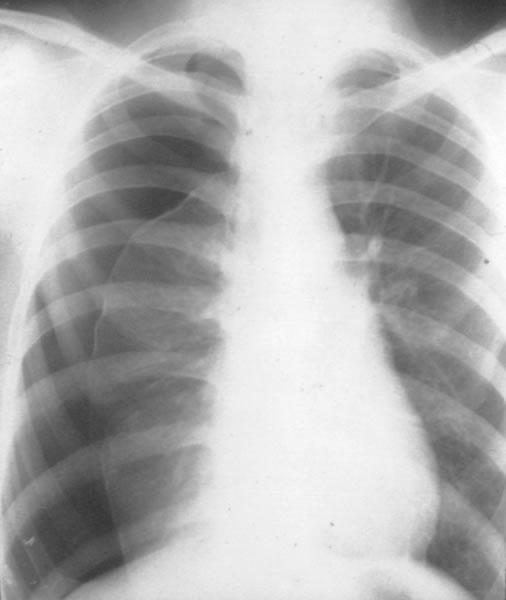

Bkel0.jpg

(506 × 600像素,文件大小:23 KB,MIME类型:

气胸

自发性气胸